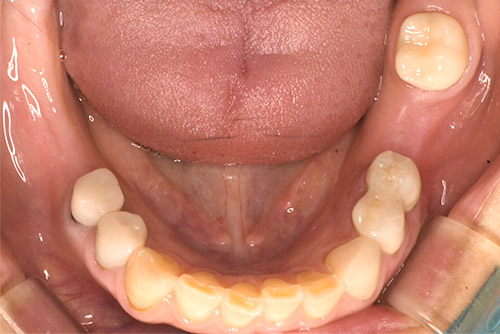

ノンクラスプデンチャー:40代 女性

治療前

治療後

| 治療名 | ノンクラスプデンチャー |

|---|---|

| 患者情報 | 40代 女性 |

| 執刀医 | 大塚院長 |

| 治療内容 | 左下欠損部を光学印象のカメラで撮影する事により型取りを行わないでノンクラスプの義歯を作製。 |

| 治療期間 | 2回(15分) |

| 費用(税込) | 330,000円 |

| 治療に対するリスク | 経年的な歯肉の変化で適合が緩くなる場合があります。 |